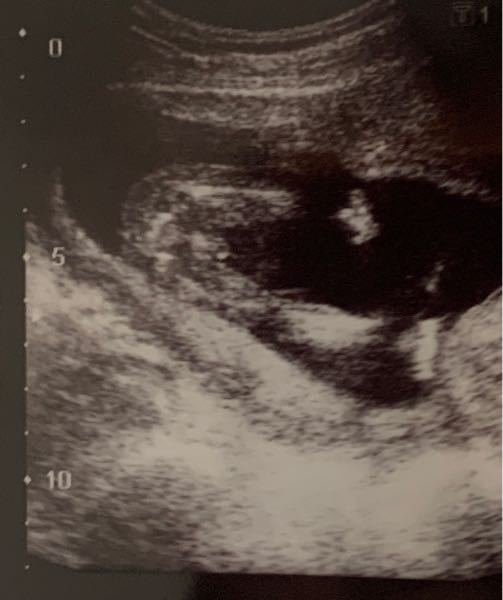

18週目 性別-妊娠18週目エコー写真・赤ちゃんの大きさ・胎動が分かる人も 妊娠18週目(18w)のエコー写真を見てみると、胎児の大きさはCRL(頭殿長)が13cm~14cm、体重は150gほどに成長、神経回路が発達する時期です。 妊娠十八週は、個人差がありますが、胎動や赤ちゃんの性別が分かる人も出てきます。 母体は、お腹も膨らみ、丸みを帯びた体形となっていくので、腰痛に注意が妊娠18週3日(18w3d)の超音波(エコー)写真 4週間ぶりのエコー検査、顔がはっきり見えてびっくり!どことなく旦那にのような。性別判定はまだだと思っていたのに男の子と判明しました! 妊婦健診2回目で久しぶりの赤ちゃんでした!

妊娠18週2日目、第6回目の検診 (性別が判明! ) 18年2月16日、妊娠18週2日目に6回目の妊婦健診に行ってきました。 1ヶ月ぶりの検診だったのですが、胎動が感じられるようになってきていたので、お腹の中の子供は元気なはず、ということで様子を見に 妊娠18週目(18w0d~6d)のエコー写真とエピソード|妊娠5ヶ月 妊娠18週は、妊娠中期といわれる時期に入り、妊娠5ヶ月目の3週目に当たります。 妊娠期間は妊娠40週までおおよそありますから、そろそろ折り返しといったところでしょうか。 だいぶママの体も徐々に体重が増え、丸みを帯びてきて妊婦さんらしくなってきました。 胎動を感じ始めたり、性別がわかっ妊娠18w0d おなまえ minimum ねんれい 32 妊娠週 18w0d 1ヵ月ぶりのエコーは、大きくなっていて画面に入らなくなっていて、驚きました♪週数通りの250g程みたいです。 足をしっかり挙げてVの字になっていて笑ってしまいました。 先生には「性別は次の検診の時かなぁ」って言われたけど、エコーの股の間には丸いものが見えたので、もしかして男の子かなぁと夫婦で

妊娠18週性別について 性別判定お願いします このエコー写 Yahoo 知恵袋

妊娠18週ぴったりのエコー写真です 性別はどちらでしょうか Yahoo 知恵袋

18週のエコーです 性別は男の子ですか 女の子ですか 教えて Yahoo 知恵袋